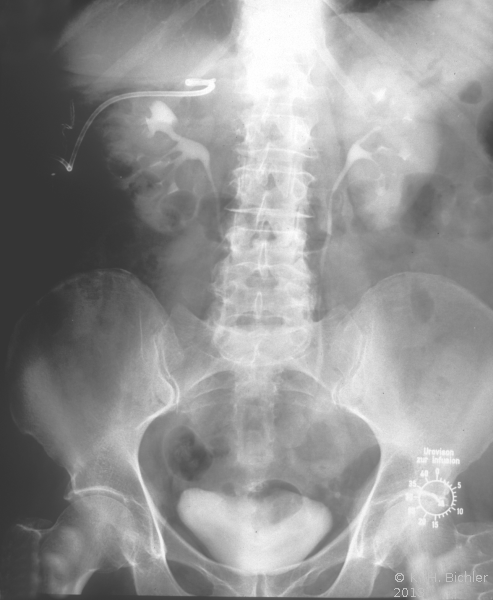

Die Patientin wurde beim Urologen wegen seit 3 Wochen persistierender Flankenschmerzen rechts vorstellig. Der Untersuchungsbefund zeigte als Auffälligkeit ein klopf- und druckschmerzhaftes Nierenlager rechts. Der Urinstatus wies keine Besonderheiten auf. Sonographisch fand der Urologe eine ca. 11 cm große einfache Nierenzyste rechts, die bis in das Nierenbecken reichte. Mit dem anschließend durchgeführten i.v.-Pyelogramm konnte eine Abflussbehinderung aus dem Nierenhohlraumsystem ausgeschlossen werden. Es waren jedoch glatt berandete, zystentypische Kelchausziehungen der oberen und mittleren Kelchgruppe zu erkennen. Der Urologe stellte die Patientin stationär in der Klinik vor. Zum Ausschluss eines eventuell vorliegenden zystischen Karzinoms wurde ein CT des Abdomens durchgeführt. Hier fand sich eine große, unkomplizierte Zyste, die die Niere verdrängte (Abbildung 4).